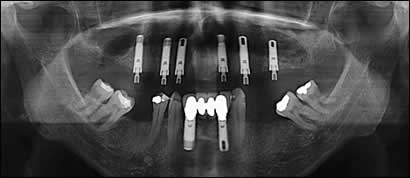

The lower incisors were removed and replaced with a fixed porcelain bridge supported by two dental implants. The implants were placed and restored with acrylic teeth the same day as the extractions. This is called “Immediate Placement and Loading”.

Fig 3: Utilizing a 3-dimensional DentaScan, Simplant software and Atlantis CAD/CAM technology, we were able to perform a “virtual” operation, placing 6 dental implants in the maxillae.

Fig 4: The 6 dental implants were placed “non-surgically”, that is, no incisions, flaps or sutures were required. There was practically no bleeding and minimal post-operative discomfort. The implants were loaded the same day with a fixed acrylic bridge.